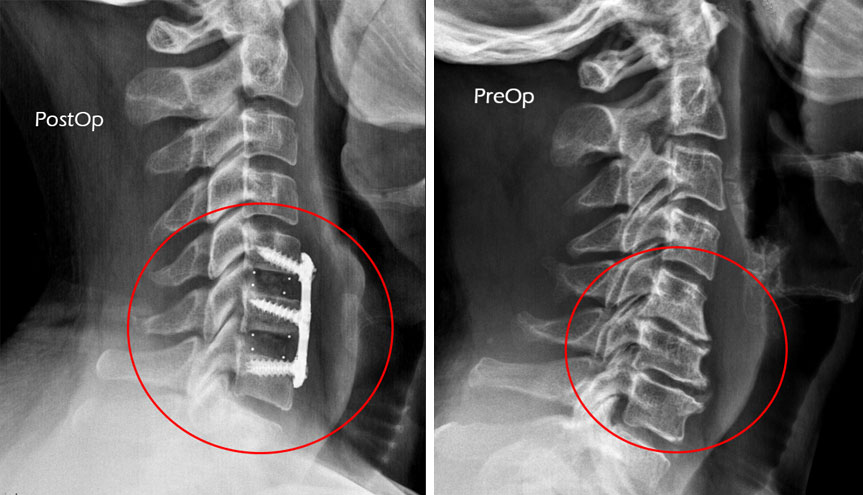

- 影響を受けた椎骨、椎間板、または神経を特定し、その領域の X 線撮影を行います(まだ撮影していない場合)。

- 椎間板を切除した領域の周囲の 2 つの椎骨にチタン製のプレートとネジを取り付けます。